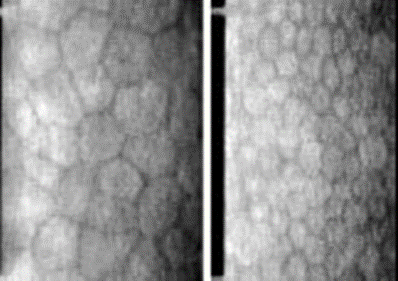

・角膜内皮障害

長年のレンズ装用による酸素不足などにより、

角膜の内皮細胞が代謝障害で脱落し大きく変形したりします。

内皮細胞は再生しないので、細胞数がある程度以下に減少すると、角膜が混濁したりする障害を生じます。(角膜内皮:角膜の内側(目の中の側)の表層)

左:内皮障害/右:正常